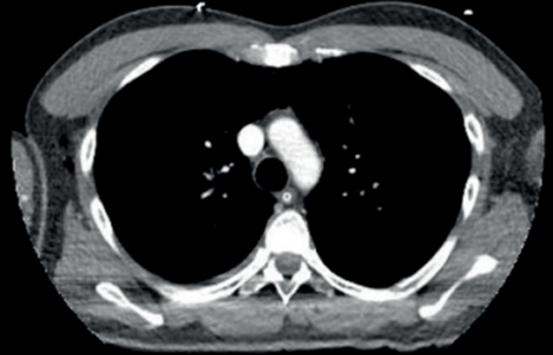

Figura1: En tomografía de tórax se observa extenso neumomediastino que diseca y se extiende a la pared derecha del hemitórax y hacia el cuello.

No se visualizan otras alteraciones parenquimatosas pulmonares (figuras2,3y4).

De la analítica a destacar: glóbulos blancos 16.000/mm3. Desarrolla insuficiencia respiratoria severa, tirajes altos y bajos, saturación de O2 67%, ingresando a unidad de cuidados intensivos. Se procede a intubación orotraqueal (IOT), murmullo alveolar ventilatorio disminuido, sibilancias en ambos tiempos respiratorios. Se conecta a asistencia respiratoria mecánica constatándose patrón de altas resistencias en vía aérea (RVA 35 m H20/l/seg, Pmax 80 cm H20), gasometría arterial con fracción inspirada de O2 de 100% revela insuficiencia respiratoria severa tipo 2, hipoxemia de 100 e hipercapnia de 149 mmhg. Se inicia sedoanalgesia continua (midazolam 1 mg/kg/hora, fentanilo 8 mcg/kg/hora), bloqueantes neuromusculares (atracurio 0,04 mg/kg/hora) por diez días. De forma complementaria dado el bronco espasmo severo y difícil adaptación a asistencia respiratoria mecánica, se recurrió a ketamina (0,3 mg/kg/min) por 72 horas. Se optimizó tratamiento broncodilatador (salbutamol y bromuro ipratropio inhalado de forma reglada) y corticoides sistémicos (hidrocortisona 100 mg cada 8 horas por 7 días), con descenso gradual en días consecutivos, logrando estabilización respiratoria con descenso progresivo de presiones en VA, mejoría progresiva del intercambio de gases. A 48 horas se realiza tomografía de control: disminución del neumomediastino y del enfisema subcutáneo, agrega zonas de enfisema en cara anterior del tórax por delante del manubrio esternal, en regiones maseteras y burbujas aéreas a nivel de espacios faringomucosos, prevertebral y neumorraquis (figuras5y6).